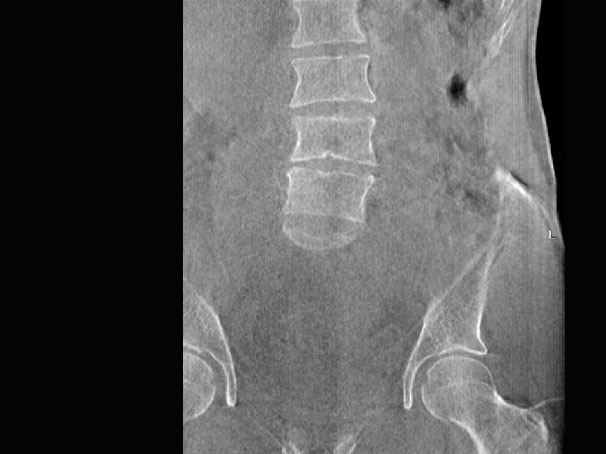

髖關節